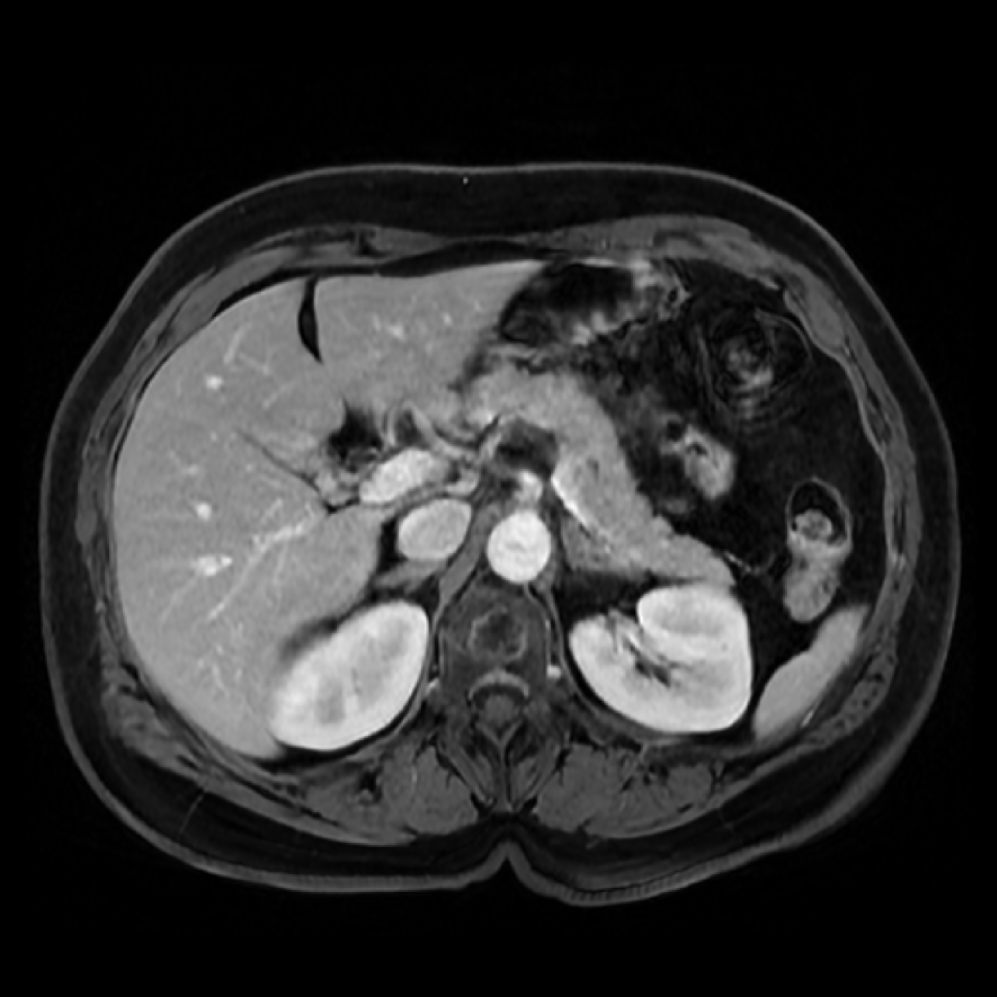

Accurate pancreas segmentation is a critical prerequisite for precise cyst analysis and classification. Recently, we developed PanSegNet [zhang2025large], a novel segmentation architecture incorporating linear self-attention layers [zhang2022dynamic] within the nnUNet framework [isensee2021nnu] to enhance global information modeling capabilities while maintaining computational efficiency (Fig. 1). PanSegNet demonstrated exceptional segmentation performance across both T1W and T2W modalities, achieving mean dice scores of 86.817.30% and 89.626.38%, respectively (Table 1, Fig. 2b-c). This performance significantly exceeded that of Swin-UNETR [hatamizadeh2021swin], one of the most used state-of-the-art transformer-based medical segmentation models, which achieved dice scores of 79.091.40% and 76.290.66% for T1W and T2W, respectively (). In this study, we integrated PanSegNet into our Cyst-X engine along with a classifier for risk prediction. In Section 2.2, we show that the choice of segmentation model affects the classification results. The performance advantage of PanSegNet was consistent across all seven medical centers, demonstrating robust generalization despite variations in imaging protocols and equipment (Table 1). This cross-institutional reliability is particularly important for clinical applications, where model performance must remain consistent regardless of imaging site or acquisition parameters.

![[Uncaptioned image]](x68.png)

Each patient was categorized into one of these three ground truth classes: no risk/control, IPMN low-risk, or IPMN high-risk. To evaluate variability in image acquisition, we applied uniform manifold approximation and projection (UMAP) to image quality indicators, revealing distinct clustering patterns by imaging center and slice thickness. This heterogeneity reflects real-world clinical variability, enhancing the dataset’s generalizability while presenting technical challenges for model development. Fig. 6 shows examples of low-grade, high-grade, and cancer developing IPMNs from the Cyst-X dataset.